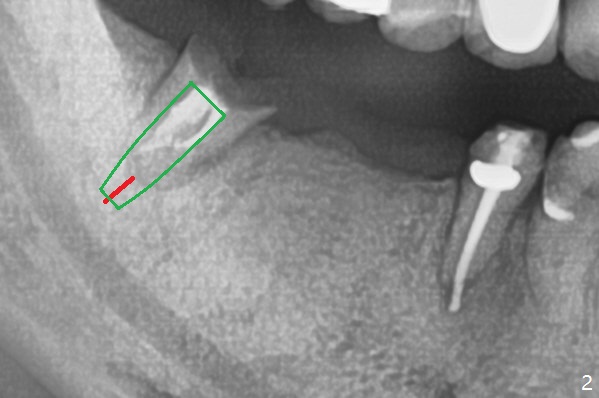

My question is have you measured the how much remaining bones are left at the extraction socket. How much bone depth is left after the root extraction? Do you think the implant could get enough fixation after the extraction? Jennifer It is a good question. As today's CT indicates (07/30/2018), there is ~ 3 mm bone for primary stability with ~ 1 mm clearance (Fig.3-6). Because of the tapered implant, ~5 mm of the implant will be able to contact the native bone if the implant is lingually placed (Fig.6). If you feel it too much a risk, still make a guide for #31 so that an anchor pin can be placed at #31 residual roots for fixation (a new idea?). Make sure that the distal portion of the guide contacts the #31 residual root stump for stability, which is superior to a guide resting on the soft tissue. I have had experience placing implants free hand in this situation. The guide will be great help. I will use judgment in surgery. The worst scenario is socket preservation. Thanks for consideration and design.